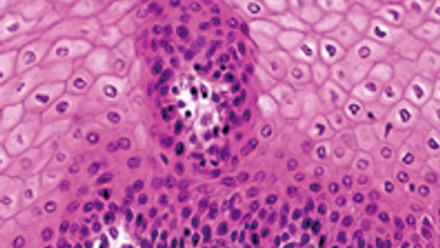

The May issue of Microbiology Today focuses on the varied interactions between humans and micro-organisms in terms of metabolism, health and disease. This issue’s feature articles focus on a range of microbes, including bacteria, viruses and fungi, looking at both the beneficial impact on human health and how they cause disease.